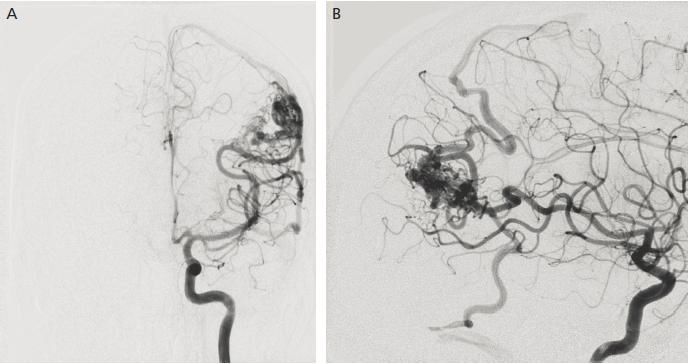

Для проведення цієї мініінвазивної ендоваскулярної операції нема потреби виконувати трепанацію черепа. Операція проводиться доступом через стегнову артерію – єдиний прокол шкіри в паховій області. По судинному руслу катетери послідовно заводяться в судини шиї, мозкові артерії і безпосередньо в порожнину аневризми.

За допомогою мікрокатетра в аневризму заводяться платинові мікроспіралі, які заповнюють її порожнину і блокують надходження крові в неї із загального судинного русла. Для відділення мікроспіралей від несучого провідника використовується електричний струм малої напруги.

В подальшому кровотік в аневризмі зупиняється, аневризма повністю тромбується і більше не несе загрози розриву.

Ендоваскулярна операція проводиться під постійним рентген-контролем на спеціальному апараті – цифровому ангіографі. Для візуалізації судин використовується йодовмісних контрастний засіб.